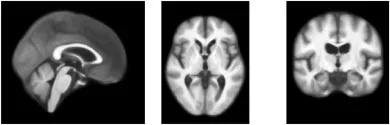

图4. 通过对训练数据中前100名受试者进行平均来构建模板。上图:通过平均获得的强度模板。下图:与平均强度模板对应的标签图。通过平均构建的模板明显不如AtlasMorph模板清晰。